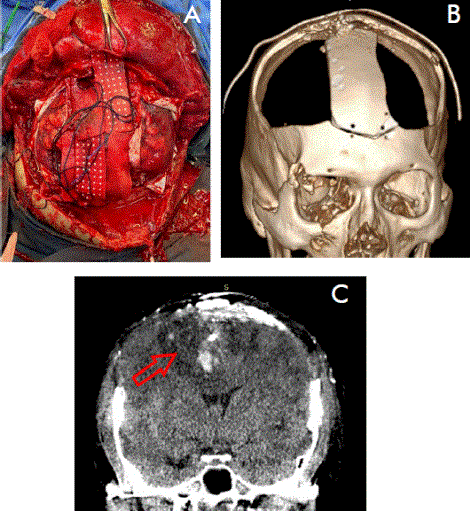

The initial diagnosis, carried out by sagittal CT scan of the skull, revealed the trajectory of the projectile and the extent of the lesion. The injury affected even the portion of the corpus callosum and cingulum. Consequently, it was decided to performed a hinge type bilateral frontoparietal decompressive craniectomy, with haematoma evacuation, without removing the bone in the midline to avoid damaging the superior sagittal sinus (Figure 2 A).

Figure 2 A) Transoperative control and B) 3D reconstruction of postoperative CT. C) Postoperative control with CT; coronal section of the skull

During the surgical procedure, a coexistence of a subdural hematoma and a cortical contusion (cortical burst) was found in the right precentral and left postcentral gyrus, accompanied by dura mater tearing. Accordingly, a complete opening of the dura mater was performed, with the portion near the superior longitudinal sinus being preserved. Bone splinters were removed, performing control of moderate bleeding within the superior longitudinal sinus by means of compression and the use of cottonoids for one hour and 30 minutes during the surgical procedure (Figure 2B).

As part of the postoperative management, the patient was referred for rehabilitation. A postoperative control was conducted one month and twenty-two days after the surgery, utilizing a CT scan of the skull in the coronal section, which revealed the re-expansion of the encephalic tissue (Figure 2C). In addition, at a follow-up appointment, the patient presented a GCS score of 11 points, left hemiparesis, with strength rated at 4/5 on the Daniels scale. He no longer required tracheostomy or gastrostomy support, exhibited oral tolerance, coherent language, and adequate vocalization, and showed no signs of complications. However, the prognosis for his function and quality of life remains guarded.